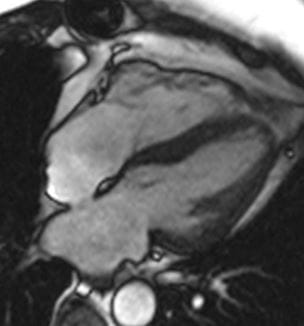

Novel Cardiac MRI Protocol Explores Impact of COVID-19-Linked Myocardial Injury

New approach captures a highly detailed assessment of heart and lung function in a subset of survivors - Innovations in Cardiovascular Medicine & Surgery | Fall 2020